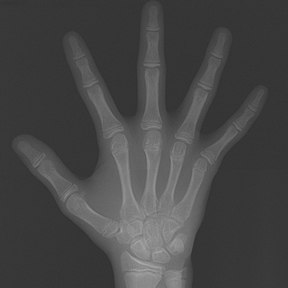

얼굴 골격의 성장에 문제가 있는지를 파악하기 위한 적절한 시기는 초등학교 입학 전인 6-7세경입니다. 이때는 유치에서 영구치로 교환되는 시기로서 부정교합 여부가 결정되는 중요한 시기이므로 이 시기를 잘 관찰하여 부정교합을 예방하는 것 또한 중요합니다. 교정의 정확한 시기는 6개월 간격으로 치과에 정기적으로 내원하여 성장 분석을 받은 후 결정하는 것이 좋습니다.